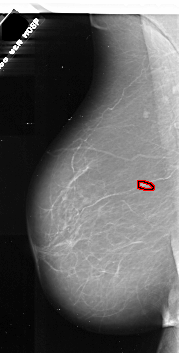

A_1073_1.LEFT_CC

FILE: A_1073_1.LEFT_CC.OVERLAY

TOTAL_ABNORMALITIES 1

ABNORMALITY 1

LESION_TYPE CALCIFICATION TYPE PLEOMORPHIC DISTRIBUTION CLUSTERED

LESION_TYPE MASS SHAPE IRREGULAR MARGINS ILL_DEFINED

ASSESSMENT 4

SUBTLETY 3

PATHOLOGY MALIGNANT

TOTAL_OUTLINES 1

BOUNDARY